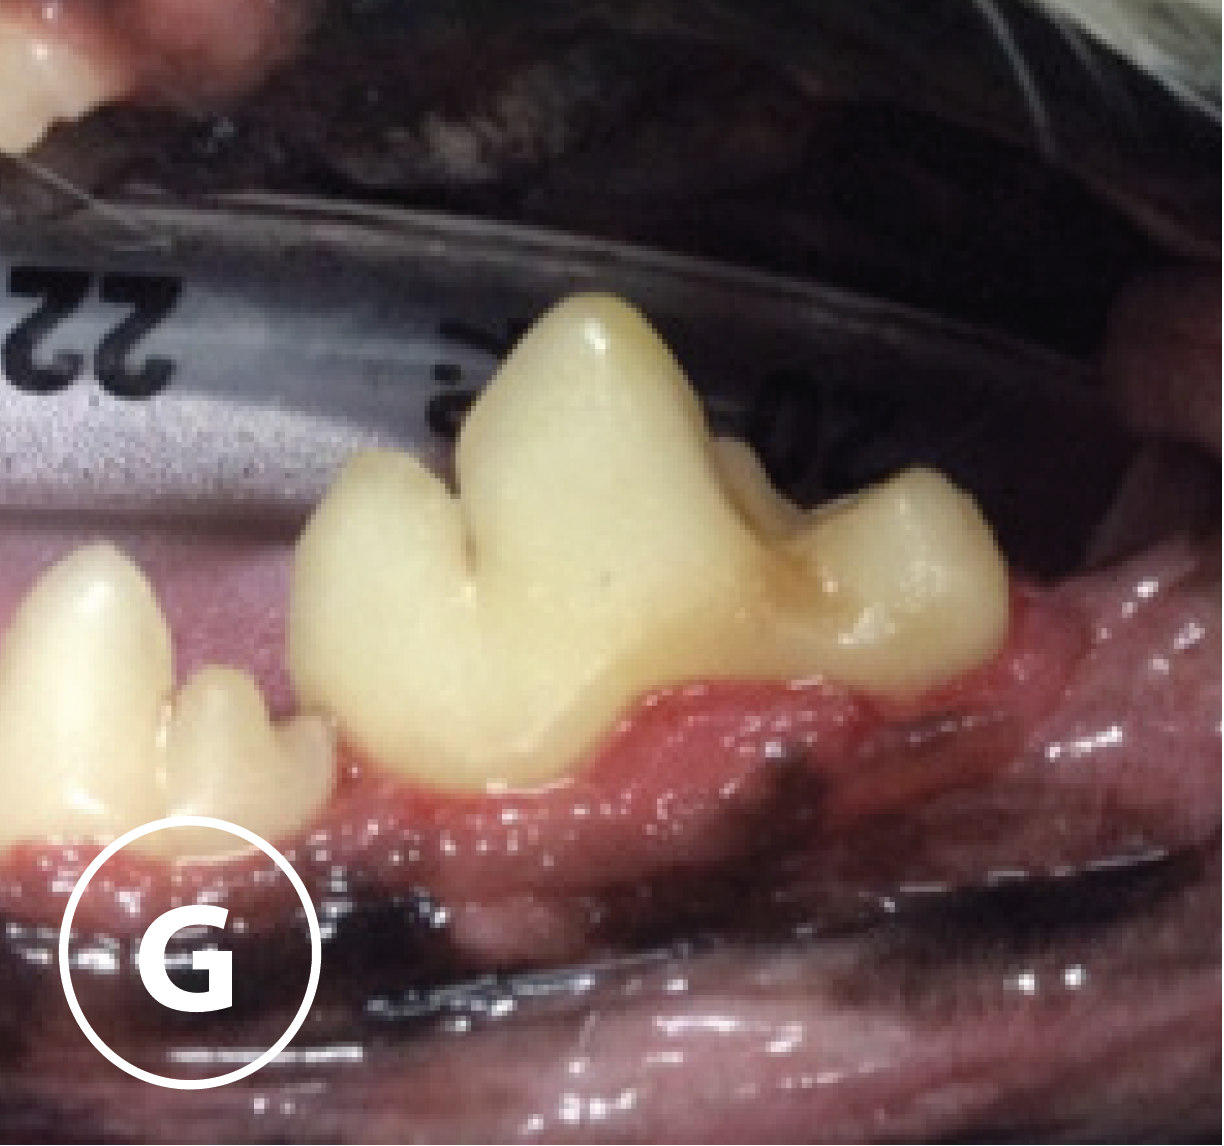

Six month follow up

Presentation

G: Photograph at 6 month follow-up showing left side of Wombat’s mouth demonstrating normal gingival height with minimal inflammation and no calculus accumulation.